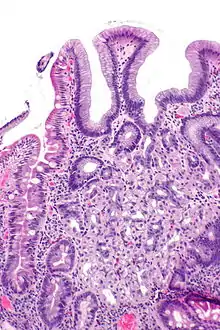

Micrograph showing a duodenal biopsy with gastric heterotopia; H&E stain

In medicine, heterotopia is the presence of a particular tissue type at a non-physiological site, but usually co-existing with original tissue in its correct anatomical location. In other words, it implies ectopic tissue, in addition to retention of the original tissue type.